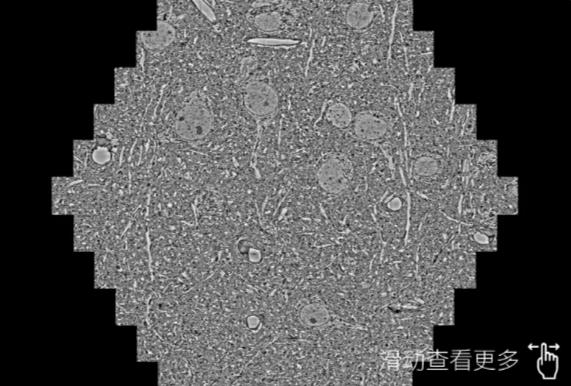

鼠脑切片。左图使用文昌蔡司文昌扫描电镜MultiSEM706对165μmx143pm面积区域成像,耗时仅需1.5秒。右图为鼠脑切片中30μm区域放大效果。样品由芝加哥大学B.Kasthuri提供。

使用蔡司高速文昌扫描电镜MultiSEM对1mm²人脑皮层组织进行高分辨成像,并对其中的各种细胞结构进行三维重构分析。左图展示了2x3mm²组织平面中锥体神经元的三维重构效果。右图显示了局部体积神经元三维重构。图像由哈佛大学chtman实验室提供,渲染图由D. Berger 制作。